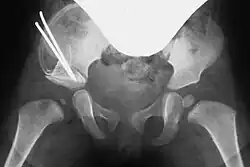

In both techniques, a suitably shaped bone wedge is inserted into the resulting gap under X-ray guidance. If needed, the wedge can be fixed with an osteosynthesis wire (Kirschner wire). The procedure typically takes 45 to 60 minutes for an experienced surgeon.[3][11]

Post-surgery, a pelvic spica cast (modified Fettweiss cast) or abduction orthosis is applied to keep the femoral head centered in the acetabulum during healing. Anesthesia is discontinued afterward.[7]

The postoperative immobilizing cast is typically worn for six weeks, with X-ray checks after one and three weeks. A cast change, often requiring additional anesthesia, is performed after six weeks. The cast is worn for three months, followed by a splint. Regular follow-up examinations are essential, with longer recovery periods for older children.[7]